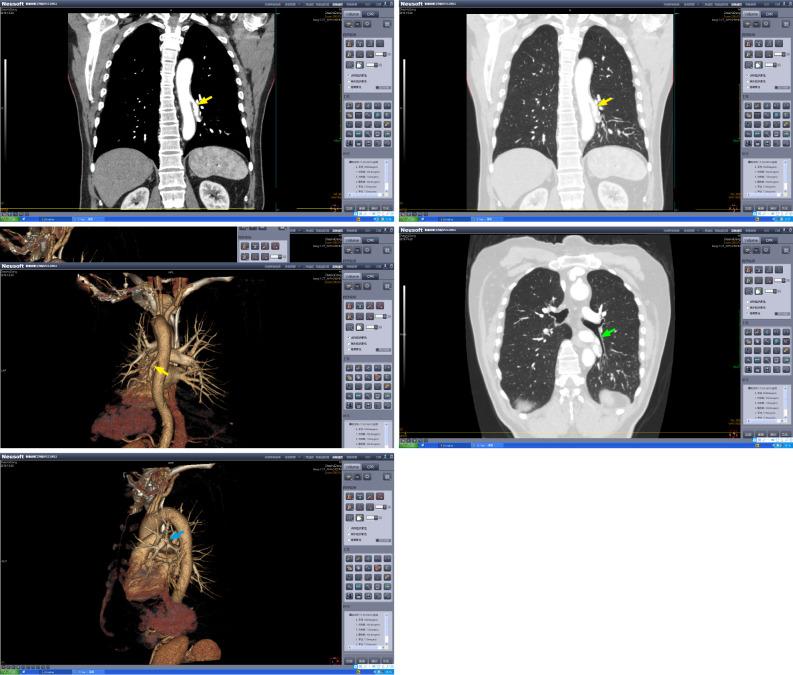

We report a 60-year-old man who presented with a history of hemoptysis for 20 d. Contrast-enhanced computed tomography of the chest confirmed the diagnosis of abnormal systemic artery to the left lower lobe, and surgical treatment was performed. The aberrant artery arising from the descending thoracic aorta was ligated, followed by removal of the left lower lobe. The patient showed good recovery and was discharged 6 d after the surgery. At the 1-year follow-up, the patient had recovered completely, and lung CT showed no abnormal findings.

我们报告一名60岁男性,有咯血20天病史。胸部增强计算机断层扫描确诊为发自体循环的异常动脉供应左下叶,并进行了手术治疗。结扎了发自胸降主动脉的异常动脉,随后切除左下叶。患者恢复良好,术后6天出院。在1年的随访中,患者已完全康复,肺部CT未显示异常。